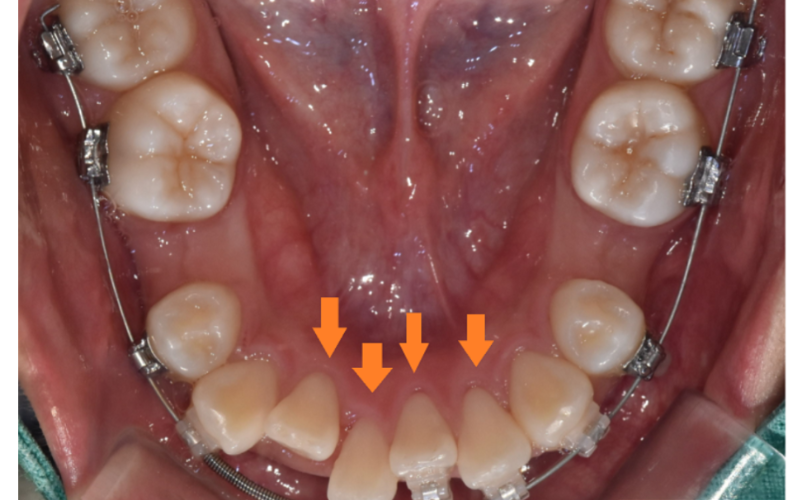

250116 치아 뿌리도 이동속도에 영향을 줍니다.

또한 치아 뿌리가 짧은 경우

교정 중 치근 흡수가 발생할 위험이 큽니다.

때문에 교정력(힘)을 약하게 주거나

속도를 늦춰서 안전하게 진행해야 해요.